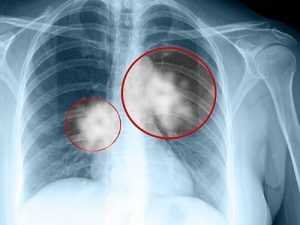

Диагностировать рак легкого можно с помощью проведения некоторых процедур:

-

Плевральная пункция

Флюорография

- Лабораторное исследование состава крови

- Бронхоскопия

- Биопсия злокачественного образования

- Плевральная пункция

- Рентгенологическое исследование

- КТ грудной клетки и брюшной полости

- МРТ головного мозга

- ПЭТ диагностирование.